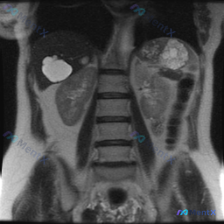

整理到一份腹部MRI冠状位T2加权图像的资料,附带提了一句“脊柱侧弯”,但实际看下来核心发现完全在肾脏上。 先把影像里的关键信息列一下: - 肝脏、脾脏、右肾看起来还好; - 左肾基本被一个大范围的病变占了,正常皮髓质结构不清,边缘也不太规则; - T2信号很杂,有明显的极高信号区(可能是液体、坏死...

刚看到一份有意思的影像资料:提问是“脾脏病变”,但提供的分析却完全是肾脏MRI T2加权冠状位的内容。整理了一下思路和发现,和大家讨论。 --- 先理清楚最核心的矛盾 首先必须明确:基于现有给出的影像信息,完全无法评估脾脏。 报告里只描述了双肾、肾盂肾盏、肾周间隙,压根没提脾脏的大小、信号或结构——...